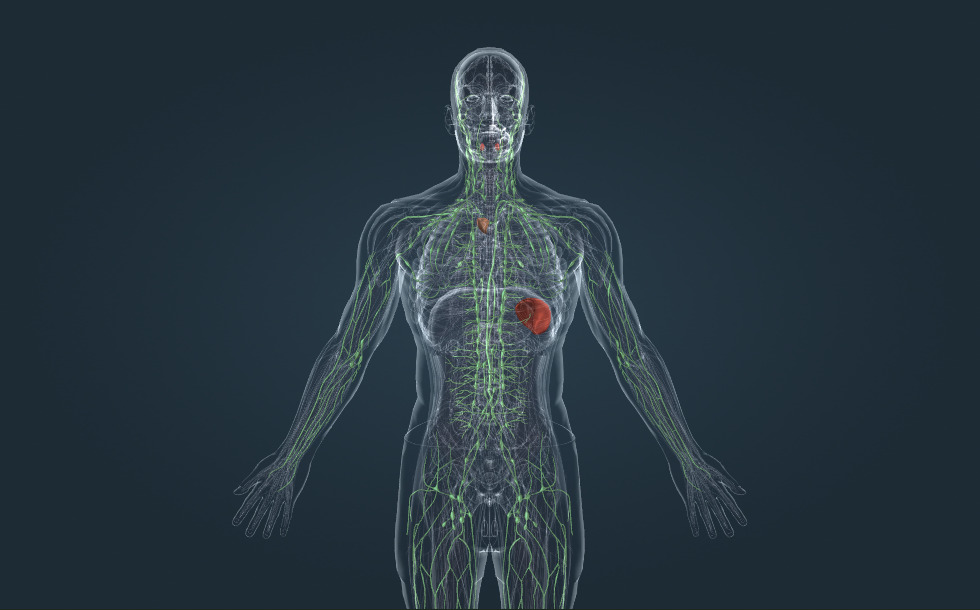

Λεμφικό σύστημα

- αμυγδαλή

- σπλήνα - Παίζει σημαντικό ρόλο στην ωρίμανση των λευκών αιμοσφαιρίων, άρα και στη λειτουργία του ανοσοποιητικού συστήματος.

- θύμος - Παίζει σημαντικό ρόλο στην ωρίμανση των λευκών αιμοσφαιρίων, άρα και στη λειτουργία του ανοσοποιητικού συστήματος.

- λεμφαδένας - Παίζει σημαντικό ρόλο στην ωρίμανση των λευκών αιμοσφαιρίων, άρα και στη λειτουργία του ανοσοποιητικού συστήματος.

- θωρακικός πόρος - Αποστραγγίζεται στην αριστερή υποκλείδια φλέβα, όπου η λέμφος αναμειγνύεται με το αίμα και μεταφέρεται στην καρδιά.

- λεμφικό αγγείο

Η λέμφος είναι το υγρό που βρίσκεται στους ενδιάμεσους χώρους, που είναι γνωστοί και ως ιστοί. Παράγεται από το αίμα, μέσω της ώσμωσης των τοιχωμάτων των τριχοειδών αγγείων. Τα προϊόντα του μεταβολισμού αποστραγγίζονται επίσης στη λέμφο. Η λέμφος μεταφέρεται στην υποκλείδια φλέβα μέσω των λεμφικών αγγείων, ενώ διέρχεται μέσω των λεμφαδένων. Τα παθογόνα που μεταφέρονται μέσω της λέμφου ανακατεύονται με τα λευκά αιμοσφαίρια που βρίσκονται στους λεμφαδένες, κάτι που είναι σημαντικό για τη λειτουργία του ανοσοποιητικού συστήματος.

Άλλα σημαντικά λεμφικά όργανα είναι ο θύμος, η σπλήνα και οι αμυγδαλές. Παίζουν επίσης σημαντικό ρόλο στην ωρίμανση των λευκών αιμοσφαιρίων και στην άμυνα του ανοσοποιητικού.

Η λέμφος είναι το υγρό που βρίσκεται στους ενδιάμεσους χώρους, που είναι γνωστοί και ως ιστοί. Παράγεται από το αίμα, μέσω της ώσμωσης των τοιχωμάτων των τριχοειδών αγγείων. Τα προϊόντα του μεταβολισμού αποστραγγίζονται επίσης στη λέμφο. Η λέμφος μεταφέρεται στην υποκλείδια φλέβα μέσω των λεμφικών αγγείων, ενώ διέρχεται μέσω των λεμφαδένων. Τα παθογόνα που μεταφέρονται μέσω της λέμφου ανακατεύονται με τα λευκά αιμοσφαίρια που βρίσκονται στους λεμφαδένες, κάτι που είναι σημαντικό για τη λειτουργία του ανοσοποιητικού συστήματος.

Άλλα σημαντικά λεμφικά όργανα είναι ο θύμος, η σπλήνα και οι αμυγδαλές. Παίζουν επίσης σημαντικό ρόλο στην ωρίμανση των λευκών αιμοσφαιρίων και στην άμυνα του ανοσοποιητικού.